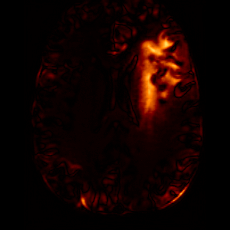

Healthy w/Lesion MaskPathologicalDifferencew/o LCGw/ LCG(a)Refer to captionRefer to captionRefer to captionRefer to captionRefer to captionRefer to captionHealthy w/Lesion MaskPathologicalDifferencew/o LCGw/ LCG(b)Refer to captionRefer to captionRefer to captionRefer to captionRefer to captionRefer to caption

Figure 7: Ablation study of Lesion Consistency Guidance (LCG). Without LCG, the generated pathological regions are indistinct and show weak pathological expression in both examples.

Lesion Consistency Guidance. Fig. 7 illustrates the impact of Lesion Consistency Guidance (LCG) for healthy-to-pathology editing. Without LCG, the generated lesion regions appear blurry around lesion boundaries, and the pathological patterns are less distinct, resulting in ambiguous lesion localization and weak pathological expression. Incorporating LCG produces lesions with more precise localization and well-defined shapes that better align with the given lesion masks, as well as textures and contrasts that exhibit stronger pathological characteristics. These results demonstrate that LCG effectively enforces lesion-aware conditioning, enhancing both spatial and semantic consistency of the generated pathological regions.